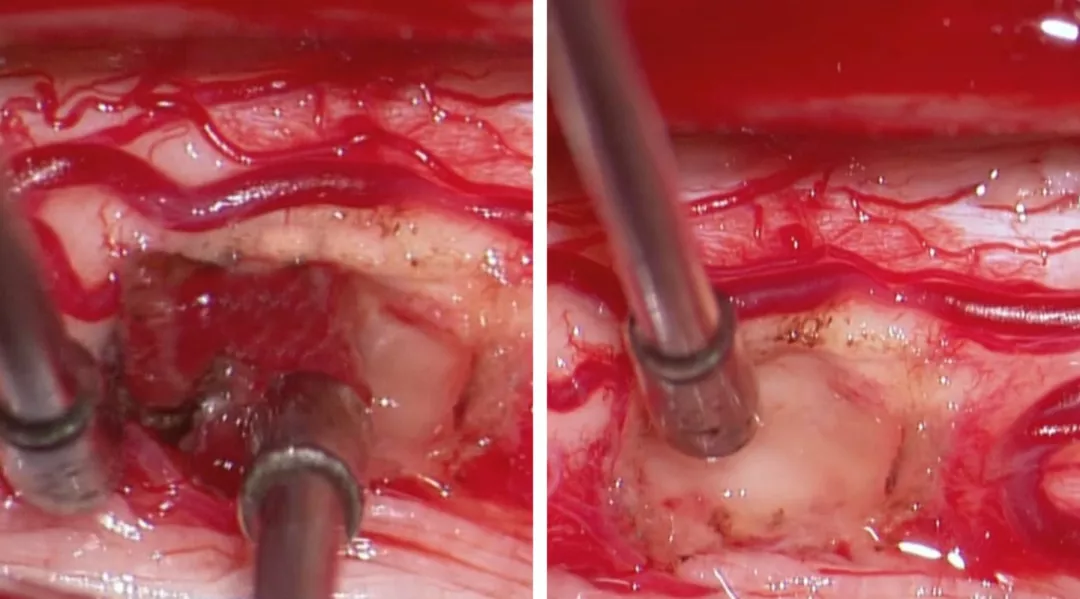

图8:血管母细胞瘤是高度富含血供的肿瘤,同时由于其组织来源为软膜血管周围间叶组织而非间质组织,因而其分离应该限于软膜而尽量避免脊髓组织损伤。鉴于其血供丰富且边界清楚,血管母细胞瘤的切除最好采用整块切除。血管母细胞瘤通常位于后外侧沟(背根入口区)。这一类似血管畸形的瘤体在分离时应仔细对瘤体进行去血供。在切除过程中,可采用小功率双极进行电凝以缩小瘤体体积从而使其界面更加清楚,易于分离。血管母细胞瘤的囊性部分或空洞可使分离更加容易。在瘤体深部与脊髓之间由于反复的小出血或压迫会造成肿瘤瘤体与脊髓也有一层界面。

切除髓内血管母细胞瘤主要包含以下几个要点:1)蛛网膜和神经根的分离、小功率双极电凝瘤体表面以及瘤体与脊髓界面的识别与分离;2)软脊膜及脊髓的切开及肿瘤的暴露,尤其是体积巨大的肿瘤;3)在处理体积较大的血管母细胞瘤时,采用6-0 prolene缝线适当牵拉软脊膜以暴露瘤体,电凝供血动脉,最后完成瘤体分离后再切断引流静脉,最终切除肿瘤。